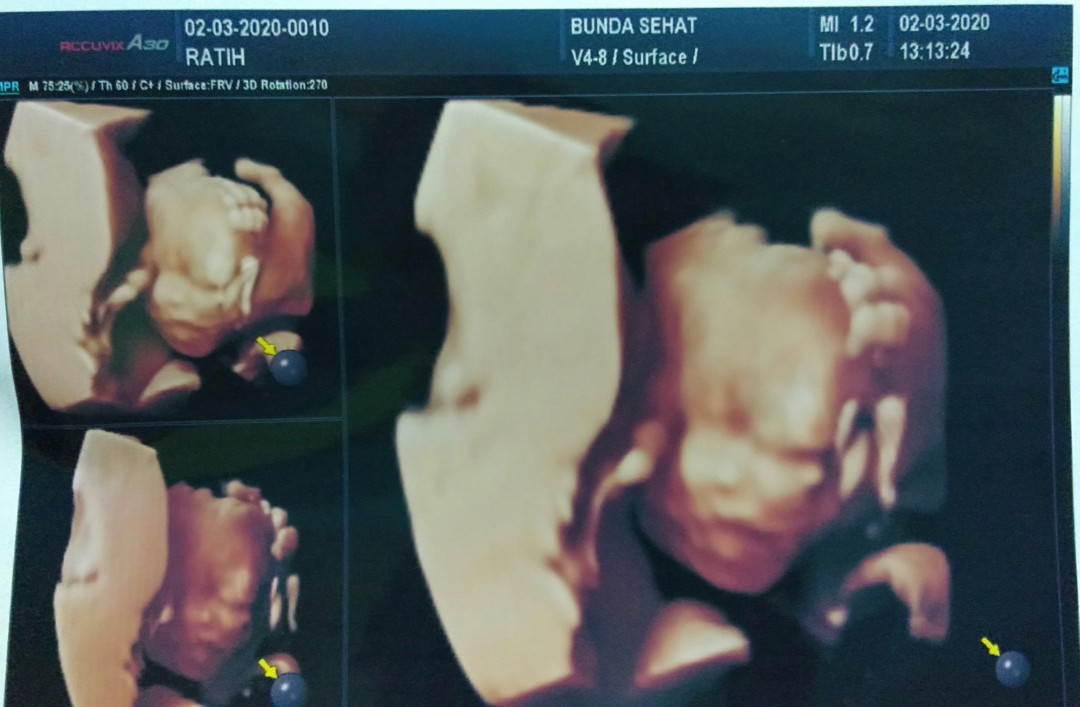

Jni usg 20-21mg bun